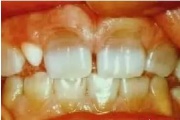

Fluoroosi

Fluoroos